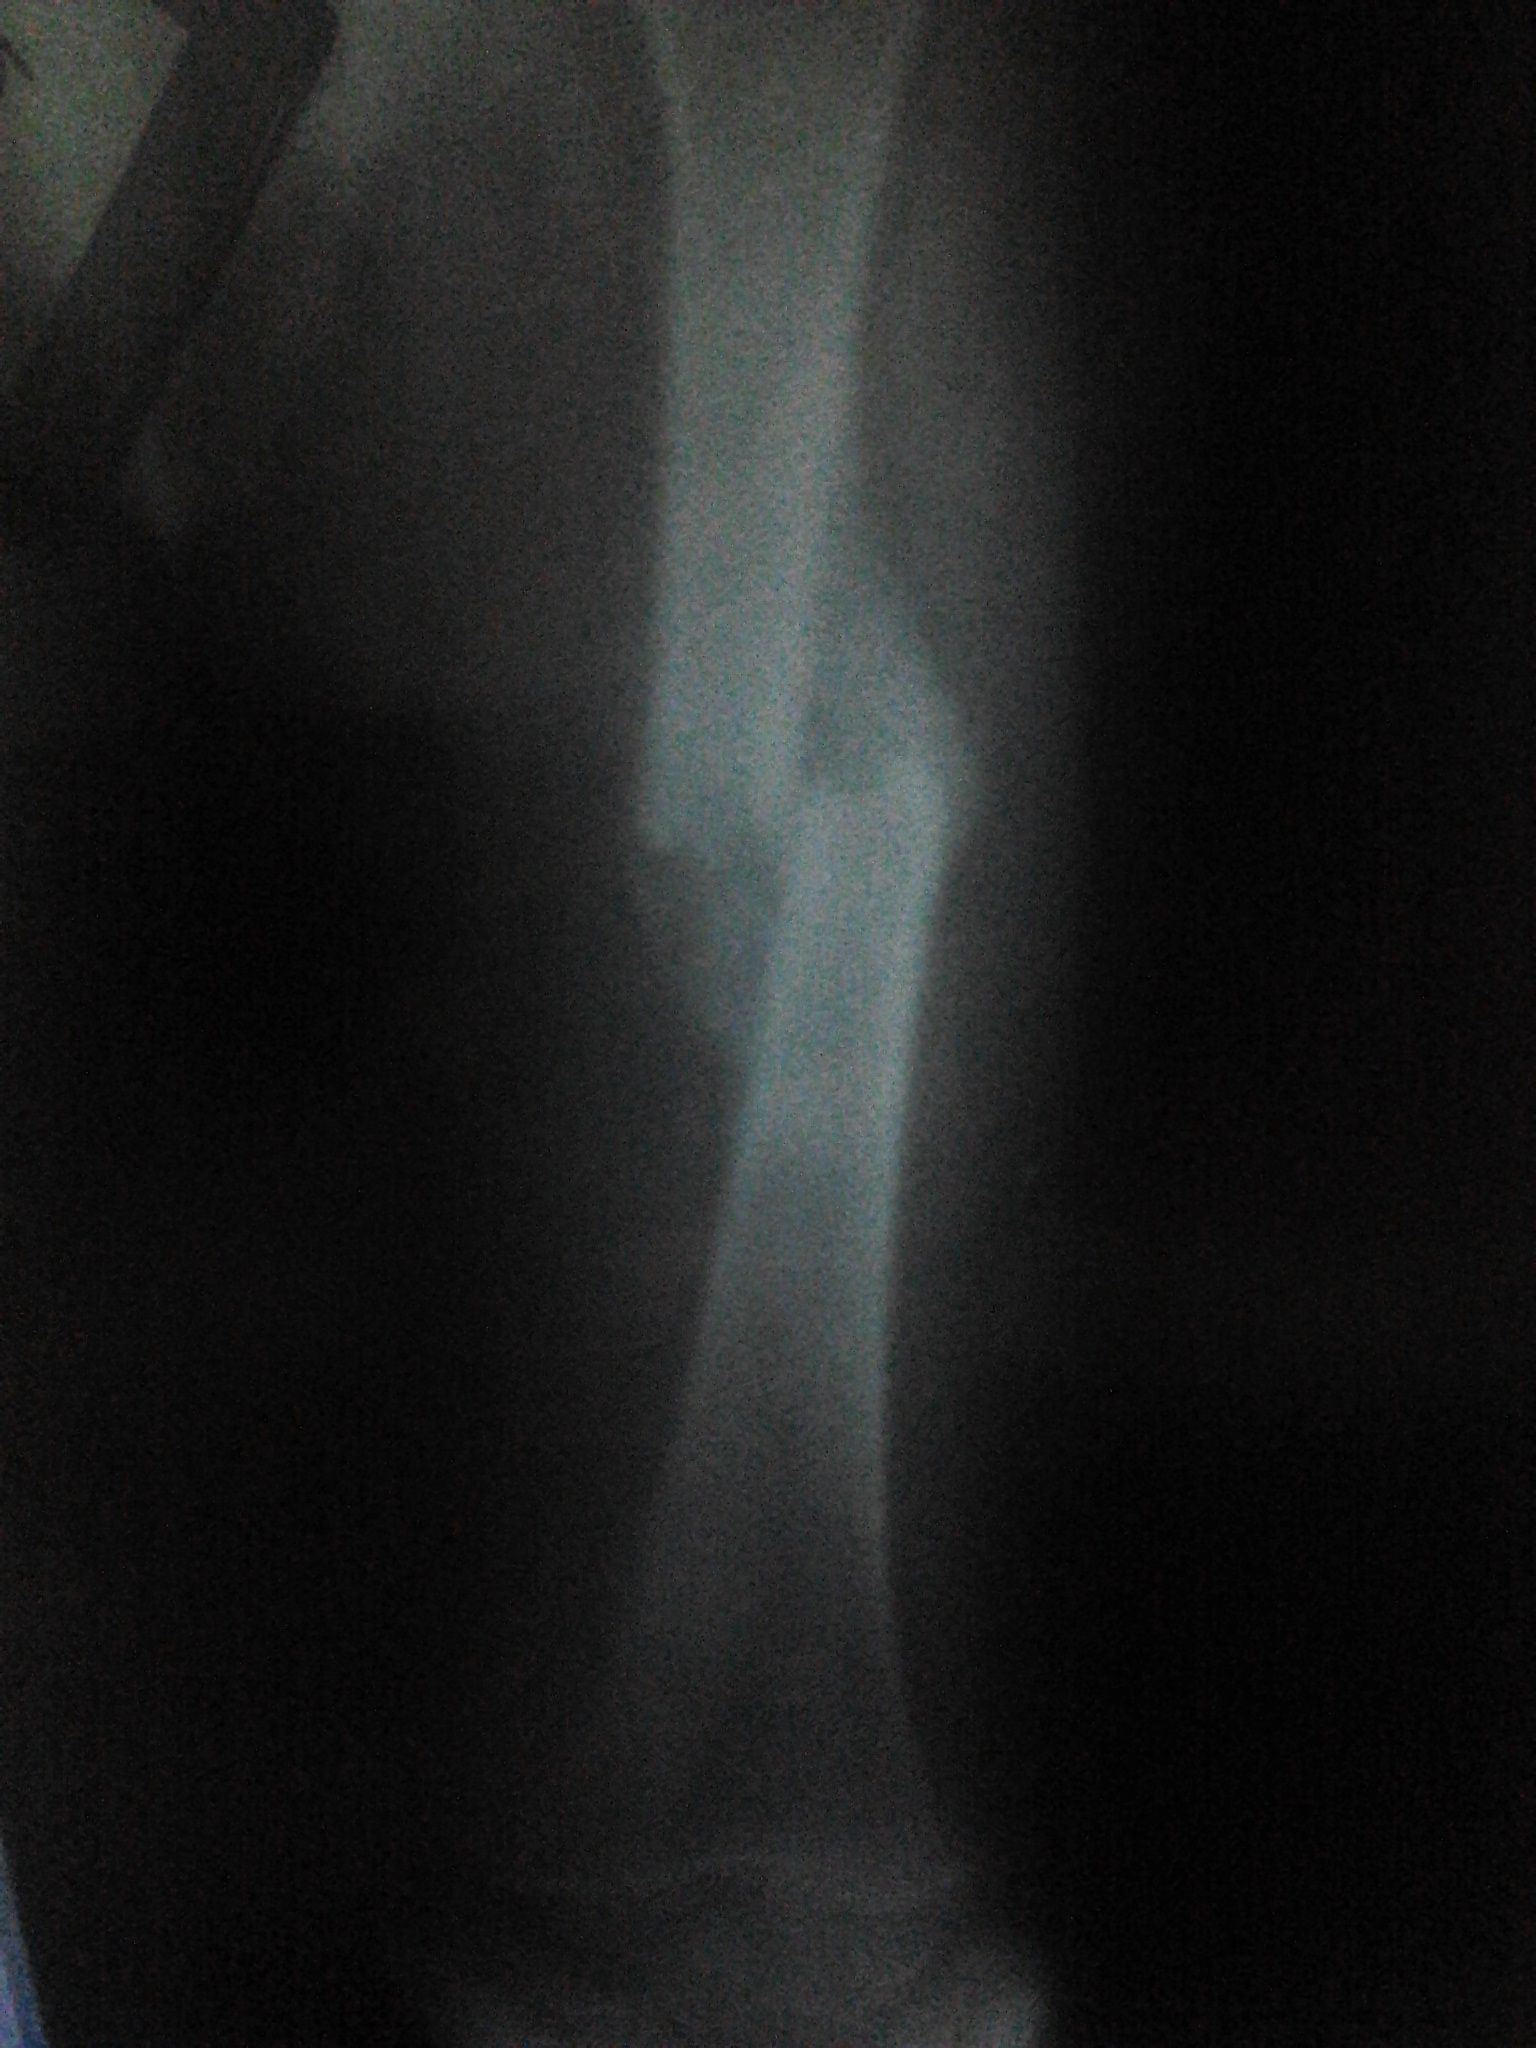

骨痂已经很明显,骨折对线非常好。小孩活动估计很好,也不会痛。不需要担心预后。

看了你的片子 是属于错位愈合 这个样子可以不再手术 因为孩子还小 等骨性愈合后随着身体长高多余的骨痂会逐渐吸收 骨头会随着力线重新塑形恢复正常 但是考虑到断端属于完全错位也不能排除以后会有稍微畸形